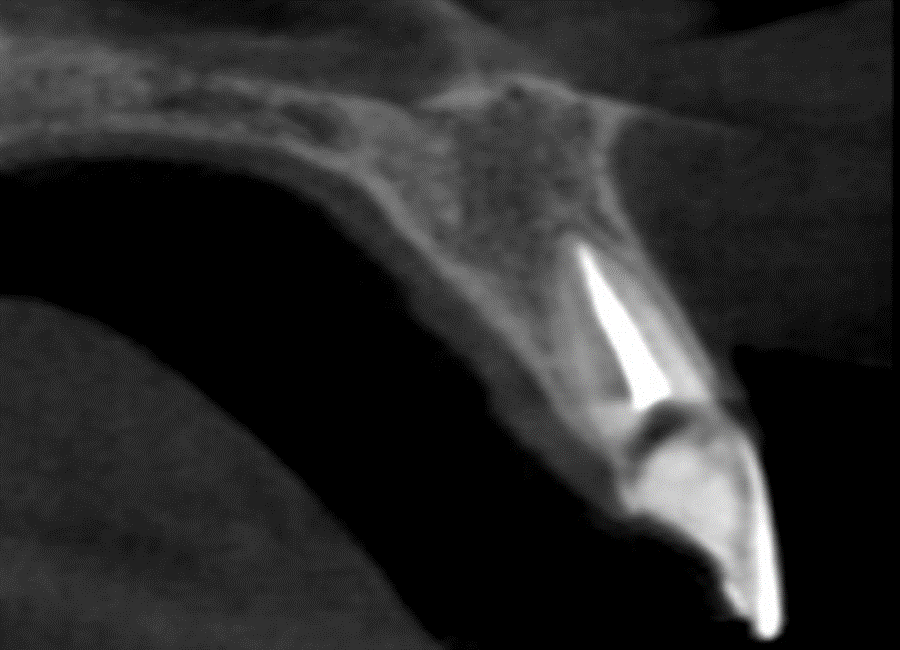

Na sequência, foi realizada uma tomografia computadorizada da maxila, e o planejamento cirúrgico foi conduzido por meio do software Blue Sky Plan, permitindo definir com precisão o posicionamento tridimensional do implante, respeitando estruturas anatômicas e a futura emergência protética.